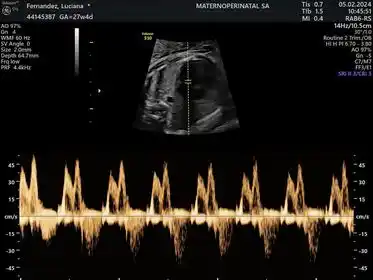

“En primera instancia el primer momento donde uno puede sospechar de alguna cardiopatía es en el primer trimestre de embarazo. Los ecógrafos han mejorado muchísimo y con un buen ojo profesional, el diagnóstico hoy tiene más certeza. Cuando nosotros hacemos el llamado “scan 11 14”, vemos por ejemplo indicadores del síndrome de Down, trisomías o algunas malformaciones, visualizamos entre otras cosas el hueso nasal, la translucencia nucal, medimos el ductus venoso, y si el ductus venoso tiene una estructura normal, ya nos está diciendo que es probable que ese bebé no tenga cardiopatía”, aclaró Cayrol.

Y continuó: “También analizamos las válvulas Mitral y tricúspide, pero fundamentalmente la tricúspide es la que marca la insuficiencia que está a veces asociada a algunas trisomías”.

También hay cardiopatías que tienen que ver con arritmias. El bebé como sucede con el adulto puede tenerlas, son mucho más infrecuentes las taquiarritmias supraventriculares, que depende si son supraventriculares o están en pasaje rápido, como en el adulto. En estos casos se le indica medicación a la madre, para que pase a la sangre del bebé a fin controlar el ritmo cardíaco, por eso hay que evaluar muy bien el medicamento que prescribe porque también afecta a la mamá.